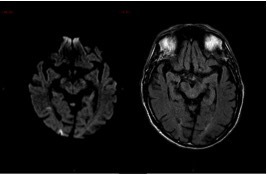

Ci-dessous des coupes axiales Diffusion et Flair de l’IRM cérébrale. La séquence T2* ne présente pas d’anomalie.

Hypersignaux diffusion à la limite de la visibilité en Flair.

L’IRM montre de multiples AVC ischémiques aigus (i. e.  6 heures), corticaux et sous-corticaux, dans des territoires artériels différents.